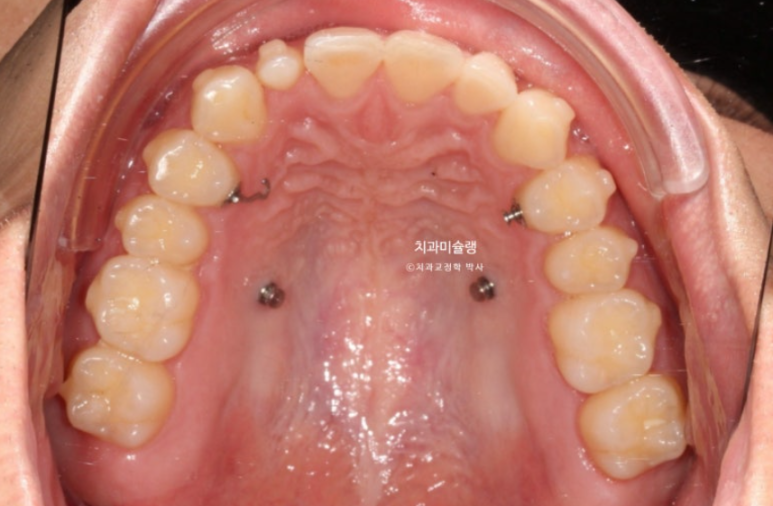

상악 어금니들을 뒤로 보내기 위해 악간고무줄, 교정용나사 등이 이용됩니다.

치료 전 후 파노라마 엑스레이를 보면 블랙트라이앵글의 원흉이었던 아래 앞니 치축 기울어짐이 해소된게 보입니다.

위 앞니 치축도 평행해졌습니다.

<인비절라인으로 뿌리 이동은 안된다.>는 잘못된 말입니다.

1년 8개월간의 치료 기간동안 치근흡수는 없습니다.

치근 평행도는 좋습니다.